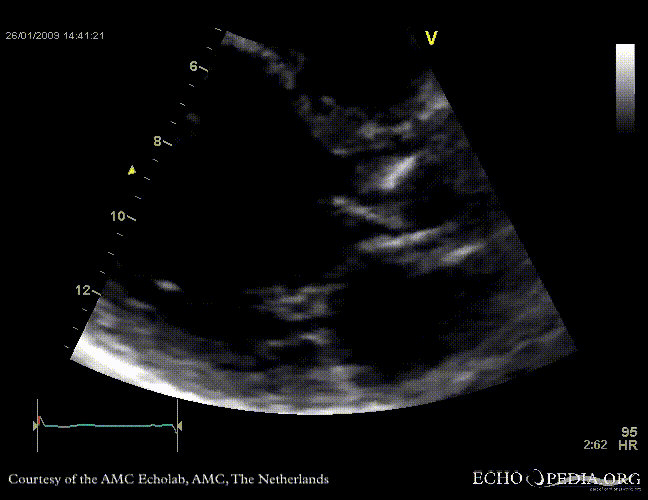

Aortic valve endocarditis with vegetation

Case description: This patient had endocarditis with an aortic valve vegetation

E00117.gif E00119.gif

PLAX aortic valve vegetation A3CH aortic valve vegetation